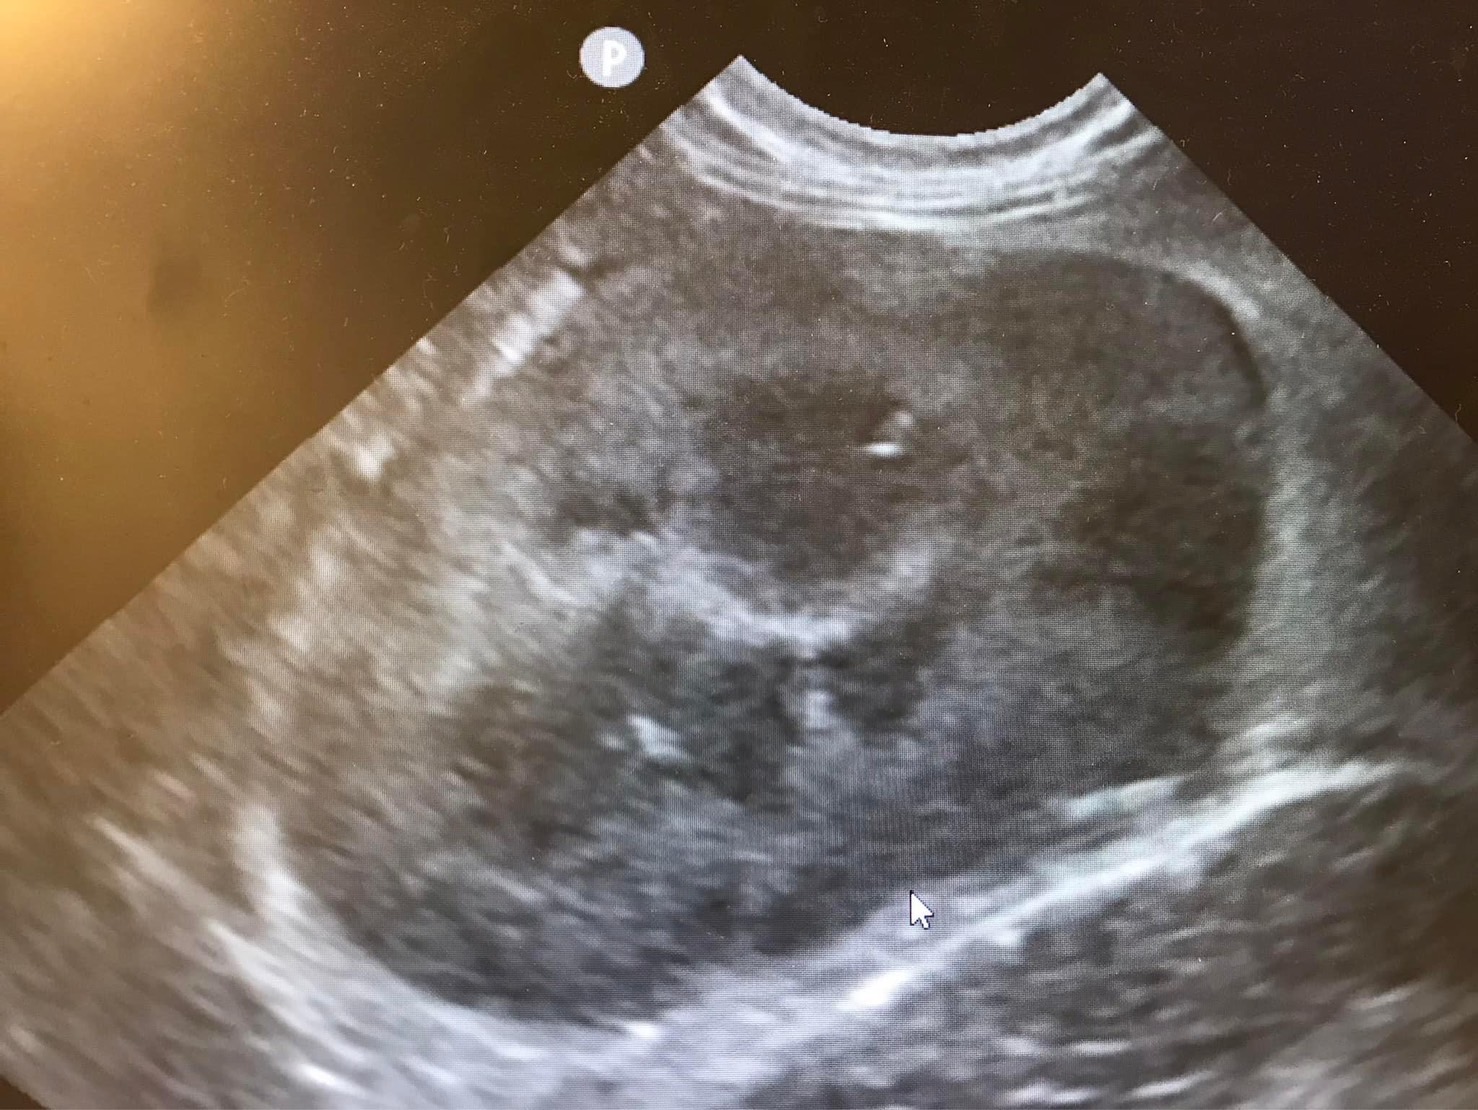

理學檢查發現小花血色蒼白,口腔牙齦嚴重發炎,靠近喉頭位置扁桃腺又紅又腫,腹腔超音波及腹腔x光影像皆發現雙腎不規則腫大。